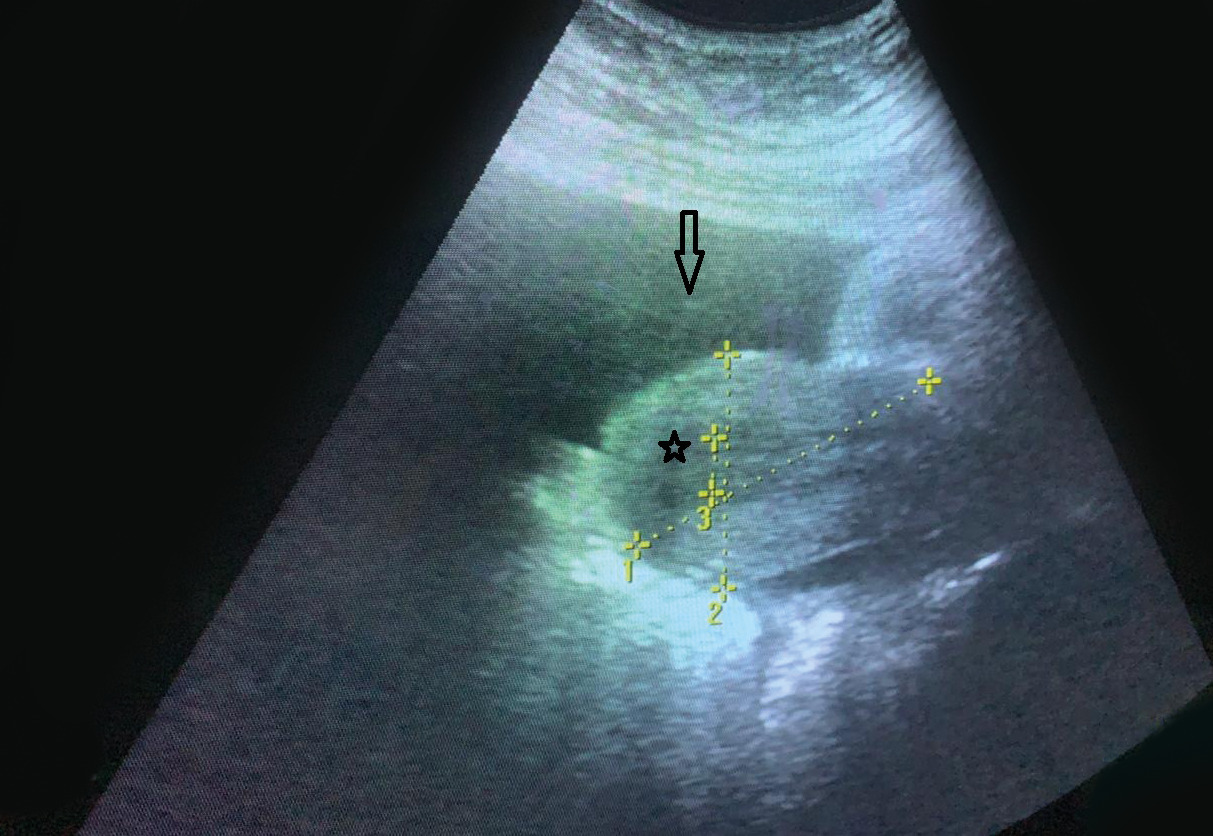

L’examen général objective une stabilité hémodynamique, une apyrexie avec une légère tachypnée (18 cycles/min) et une masse abdomino-pelvienne palpable jusqu’à mi-chemin de l’ombilic. Une échographie montre un utérus de taille normale, un endomètre à 8 mm, un ovaire droit non vu, un ovaire gauche siège d’une image à double composante solido-kystique, irrégulière, d’échostructure hétérogène, polylobée, mesurant 10 cm de grand diamètre, avec une interruption significative du signal Doppler en regard. On note la présence d’un épanchement liquidien de moyenne abondance, siégeant au niveau des deux culs-de-sac vésico-utérin et de Douglas (fig. 1). Le bilan biologique relève un taux de β-hCG plasmatique négatif, un hémogramme dans les normes, une protéine C réactive (CRP) normale et un taux sérique de CA- 125 élevé (276 UI/mL). Un cliché radiographique thoracique réalisé en raison de la gêne respiratoire montre un épanchement pleural gauche de faible abondance.